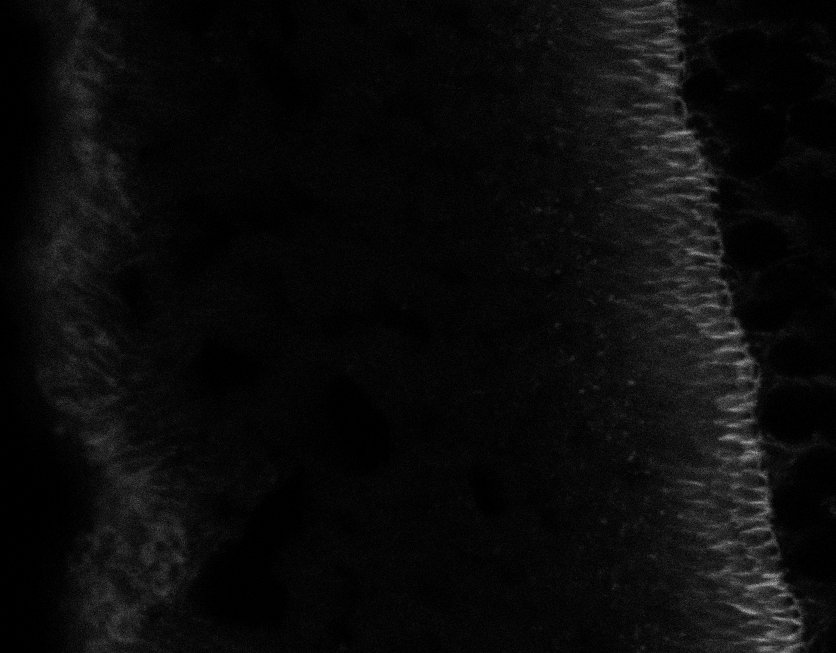

Tubulin

Tubulin - Bip

Tubulin - Nuc